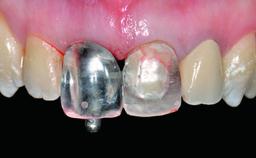

Replacement of a Failing Upper Left Central Incisor: Immediate Placement of an RC Bone Level Implant and Provisionalization

A healthy 23-year-old female patient was referred for a consultation on replacing tooth 21 with an implant-supported restoration. The patient had recently moved to the area and reported a history of endodontic and periodontal treatment for tooth 21. The tooth had been deemed non-restorable by her previous periodontist but since she was going to be moving, he recommended consulting to a dentist in her new city to continue her treatment. A review of her medical history yielded no significant findings and no known drug allergies. The analysis of her smile revealed a medium to high symmetrical smile line and a slightly discolored tooth 21.

Lip Line No exposure of papillae Exposure of papillae Full exposure of mucosa margin

Soft Tissue Contour and Volume Ideal